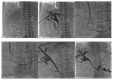

Methods: Twenty-nine patients (22 men, 7 women; mean age of 60.7 (range 33-88) years) diagnosed with dysfunctioning PBE were included. Percutaneous transhepatic biliary drainage and subsequent PBE dislodgment into the bowel were performed in all cases. Patient demographics, etiology of the biliary stricture, indication, technical success, complications, and clinical outcomes were gleaned from medical records.

Results: Seventeen patients had malignant strictures, while 12 patients had benign conditions. A total of 36 PBE (33 straight, 3 double-J) were treated. Six patients had more than one PBE. Successful dislodgement of the PBE was achieved in 28 (96.6%) of the cases. Monorail threading was performed in 8 cases while dislodgement by balloon friction was utilized in 21 patients. There was no statistical significance between benign and malignant biliary strictures regarding dislodgement duration (p = 0.080). No major complication was encountered. Thirteen minor complications in 10 patients including abdominal pain (n = 8) and mild hemobilia (n = 5) were observed and treated conservatively. Uneventful passage of the PBE was reported by all patients with technical success.